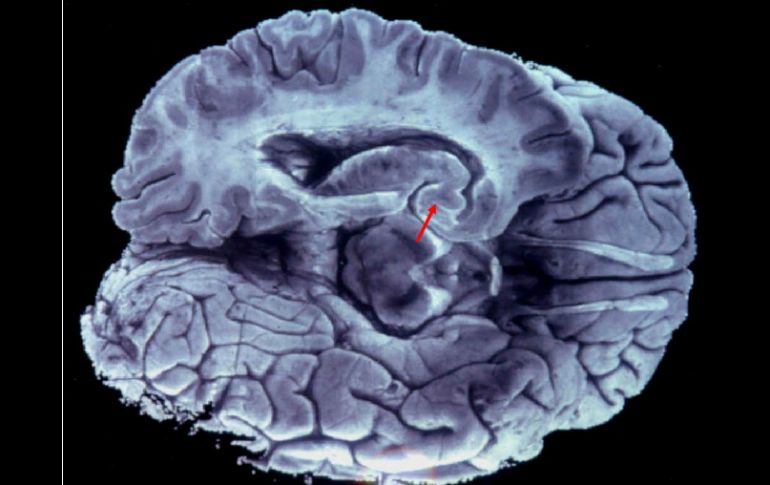

Tecnología | Desempeñan un papel crucial en tres de los tipos de cáncer de cerebro más comunes Mutaciones en gen de la inmortalidad generan tumores cerebrales Desempeñan un papel crucial en tres de los tipos de cáncer de cerebro más comunes, ya que las células malignas pueden proliferar Por: EFE 19 de marzo de 2013 - 07:04 hs Una enzima, la telomerasa, opera como un factor de crecimiento que permite que la célula continúe proliferando. EFE / WASHINGTON, ESTADOS UNIDOS (19/MAR/Y2013).- Las mutaciones identificadas recientemente en un gen que hace que las células sean inmortales desempeñan un papel crucial en tres de los tipos de cáncer de cerebro más comunes, según un artículo que publica hoy Proceedings of the National Academy of Sciences. Las conclusiones a las que llegó un equipo de investigadores encabezado por el Instituto Duke del Cáncer, y que incluyen a cánceres del hígado, la lengua y las vías urinarias, explican cómo algunas células malignas pueden proliferar en tanto que las células normales se debilitan y mueren. Esta clave para la inmortalidad involucra a los telómeros, los extremos de los cromosomas que impiden que estos se adhieran unos a otros o se quiebren. Cuando las células normales se dividen los telómeros gradualmente se acortan hasta que son tan pequeños que las células dejan de dividirse y mueren. Una enzima, la telomerasa, opera como un factor de crecimiento que mantiene, temporalmente, la longitud de los telómeros y permite que la célula continúe proliferando. Los científicos han descubierto recientemente que las mutaciones en el gen promotor TERT, el cual controla las instrucciones para la producción de la telomerasa, está involucrado en algunos tumores cancerosos. Al parecer, esa mutación del gen promotor TERT, esencialmente, crea un ímpetu de crecimiento constante de forma tal que los telómeros jamás se acortan y la célula puede dividirse por siempre. La investigación a la cual se refiere este artículo en PNAS ha ampliado aquellos descubrimientos con el análisis de más de mil 200 tumores en 60 tipos diferentes de cáncer. El equipo investigador lo encabezó Hai Yan, profesor de patología e investigador en el Centro Preston Robert Tisch de Tumor Cerebral, en la Universidad Duke, e incluyó a colaboradores del Hospital John Hokpkins y otras instituciones. Los investigadores casi no encontraron mutaciones en TERT en muchos de los tipos principales de cáncer, incluidos los de mama y próstata, lo cual indica que un factor todavía desconocido hace que los telómeros se alarguen y promuevan la inmortalidad de las células en esas enfermedades. Pero el equipo también identificó nuevos tipos de tumor altamente asociados con las mutaciones del promotor TERT. Estos cánceres en general comparten una característica: surgen en tejidos con tasas relativamente bajas de renovación celular, lo cual sugiere que necesitan la mutación para iniciar la producción anormal de telomerasa. Estos tipos de cáncer incluyen melanomas, liposarcomas, carcinomas hepatocelulares, carcinomas de célula transicional en las vías urinarias, carcinoma espinocelular de la lengua, blastomas medulares y subtipos de gliomas, incluido el 83% de los glioblastomas primarios, el tumor cerebral mas común en los adultos y con una supervivencia promedio de solo 15 meses. Temas Cáncer Ciencia médica Células Tumor Lee También Cómo podrían los antibióticos incrementar el riesgo de cáncer colorrectal Conmociones cerebrales, la cuarta lesión más frecuente en partidos de la Conmebol Estudio chino revela una mutación que eleva riesgo de alzhéimer Esta terapia podría revolucionar el tratamiento oncológico en Latinoamérica Recibe las últimas noticias en tu e-mail Todo lo que necesitas saber para comenzar tu día Registrarse implica aceptar los Términos y Condiciones